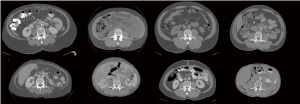

In general, cross-sectional analysis of single CT images, typically landmarked at the 3rd lumbar vertebra (L3) (Figure 1) is conducted. Muscle cross sectional area (cm2) in single axial images at this level were shown to have a good correlation with while body muscle volume (r2 =0.85) by Shen et al. (18). Whole body imaging is rare in clinical oncology; an approach using L1 has been suggested for patients with thoracic imaging only (19,20).

Diagnostic imaging allows detailed assessment of the individual cachexia trajectory. The person illustrated in Figure 1 had a diagnosis of metastatic breast cancer. Compared to time of diagnosis, she lost 10.5% of muscle by year 2 and 29.1% by year 3 (end of life). A transient gain of visceral fat (+93%) and subcutaneous fat (+8%) was seen at year 2, but by end of life 72% of baseline visceral fat and 62% of subcutaneous fat had been lost.

An international consensus of clinical experts (1) defined cancer cachexia as “…being characterized by loss of muscle, with or without loss of fat mass”. The concurrent loss of muscle and gain in fat of the patient in Figure 1 typify this statement. The eventual result of such changes, sarcopenic obesity, is not uncommon in patients with advanced cancer. Sarcopenia and muscle wasting are endemic in patients with advanced cancer in westernized countries, but the same populations are afflicted with epidemic obesity. Literature on sarcopenic obesity in patients with locally recurrent or metastatic cancers was recently summarized (21). The overall prevalence of sarcopenic obesity was 9.3% (range, 2.3–14.6%), and 24% (range, 5.9–39.2%) of patients with a BMI >30 kg/m2 were sarcopenic. As also summarized by these authors, sarcopenic obesity associates with exceptionally poor clinical outcomes, including complications of cancer surgery, chemotherapy toxicity and mortality.

Each patient’s experience of cancer cachexia is uniquely defined by their pre-illness body habitus and their specific trajectory of loss (Figure 2). Levels of adipose tissue in subcutaneous and visceral compartments are highly variable among individuals, as is muscularity. Rate of muscle loss over time associates with mortality. For example, Blauwhoff-Buskermolen et al. (22) showed that in metastatic colon cancer, the patients with the highest rate of muscle loss (>9%) during a course of palliative chemotherapy, had the highest mortality.

While we know that some patients with cancer have sarcopenia at diagnosis [e.g., (10)], the year of death is the period in which the most striking catabolic losses of muscle ensue (45,57). This is illustrated by CT images (Figures 1,2); images from the end of life show that some patients have become frankly emaciated. In our setting, about one in five patients with advanced cancer reach this body habitus. In current paradigms of care, a patient entering the year of death is likely to be an outpatient at a cancer center or hospital, in the charge of an oncologist, receiving chemotherapy and have access to referral for supportive care in various forms within the institution. Towards the end of the year of death, treatment may or may not still be ongoing (63), and referral for palliative care is likely to have occurred. Muscle wasting and cachexia are not generally a primary focus of oncologists, and the opportunity for early identification and intervention can easily be lost. Referral to palliative care still occurs late in the disease trajectory for many patients, at which time cachexia and its associated muscle wasting may have reached the refractory stage. There are current calls for the integration of oncology and palliative care (64): the year of death trajectory of cancer cachexia is but one example of the need for integration, in this case of diagnostic imaging, human and experimental biology, supportive and palliative care, clinical nutrition, clinical pharmacology and oncology.